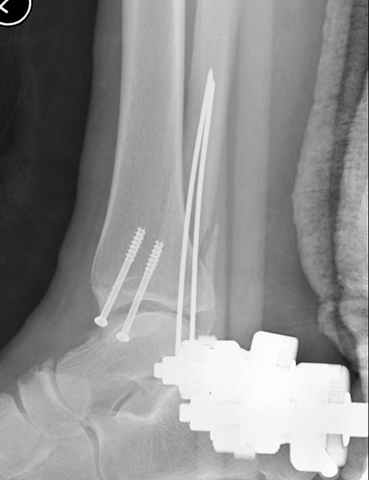

This is a pilon fracture. I suggest fixation of the fibula with a one-third tubular plate and a joint spanning external fixator on the medial side as initial treatment. If the tibial articular surface cannot be reconstituted, the patient will require an arthrodesis.

I would suggest to fix the fibular fracture at the very beginning and under fluoroscopical control and axial traction try to restore articular surface stabilizing percutanously by K wires and cannulated screws, type of external fixation to be used is up to your preference.

A propos fibular fixation if one is eager to stabilize it separately. In the fracture pattern a way of closed fixation by V-shaped stressed wire (advanced by colleagues from Moscow, prof. Lazarev A.F. et al.) must be excellent. We use indirect closed reduction by the external fixator. Example attached, that fibular fracture is even more suitable for plating but the wire did the job.